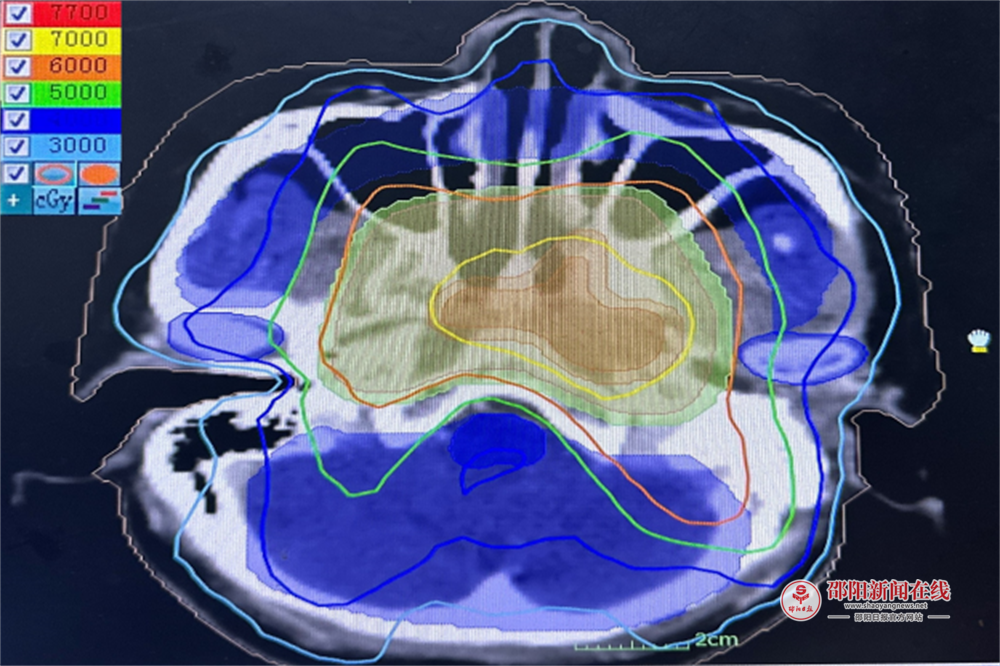

团队采用调强适形放疗(IMRT)联合同步化疗方案,邀请影像科专家共同精准勾勒鼻咽部肿瘤边界,实现 “肿瘤区域高剂量聚焦、颅底及咽旁间隙等关键部位低剂量保护”。针对鼻咽癌易侵犯周围组织的特性,医生为每位患者定制个体化靶区,使射线像 “手术刀” 般精准清除病灶,显著提升了局部控制率和生寸率。